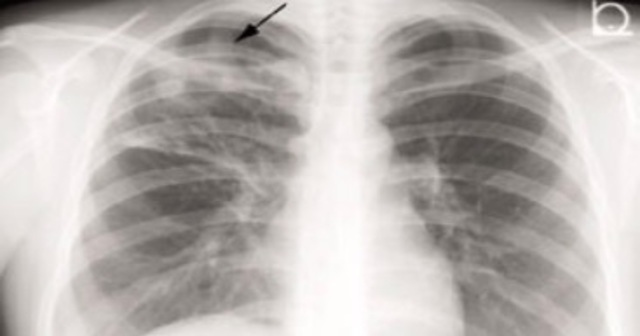

結核の皮膚検査または血液検査は、喀痰培養検査または塗抹検査と同様に、通常、陽性結果をもたらします。胸部X線検査でも異常が見つかる場合があります。

結核の治療を受ける人は通常、医療専門家との面会に数回出席する必要があります。予約には、薬が有効かどうか、また他の人に細菌を感染させる可能性があるかどうかを判断するための検査が含まれる場合があります。検査には、胸部X線検査や痰の臨床検査が含まれる場合があります。